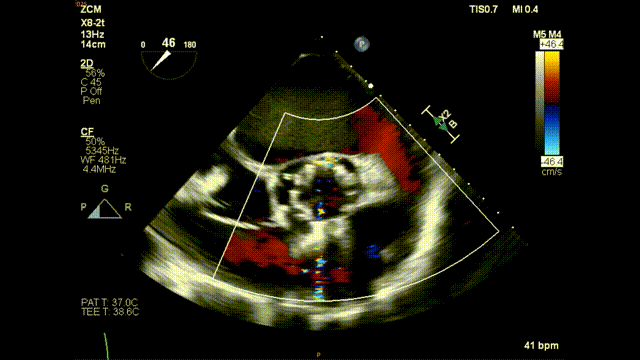

术前食道超声示:

术前食道超声-短轴color

术前食道超声-短轴 color